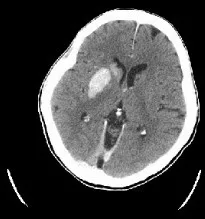

患者在发病80分钟时完成CT平扫,显示右侧颈动脉及大脑中动脉(MCA)M1段、M2段高密度征,提示血栓非常长;ASPECTS评分10分。

术后即刻CT,发现造影剂部分外渗。

24小时复扫CT,造影剂外渗完全消失。